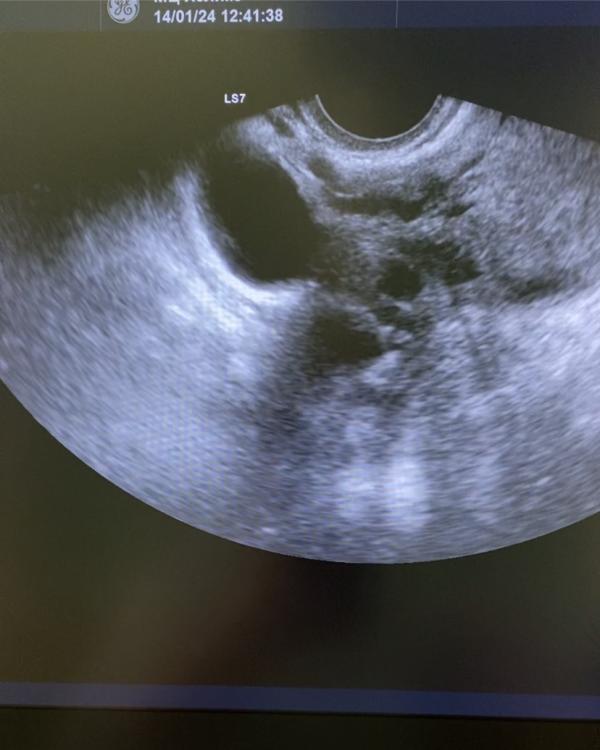

Этим постом хочу предостеречь женщин от самостоятельного прерывания беременности.

Основной довод женщины , что она всегда так делает и было всё хорошо 😭 ( 8 абортов)